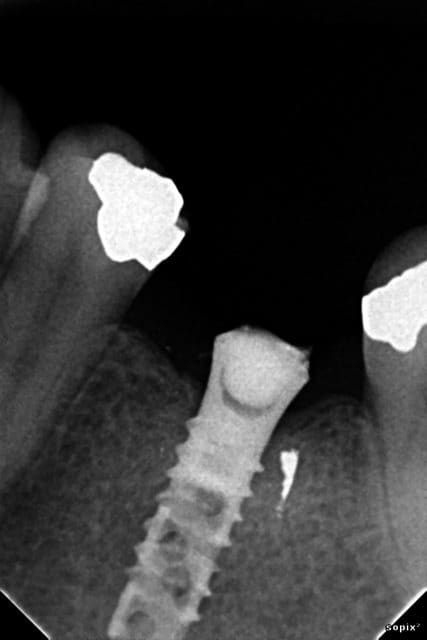

Bonjour, qui arrivera à identifier cet implant posé il y a 20 ans avec vis cassée dedans ?

un ancêtre de Straumann ?

ITI Hollow screw implant.

c'est compatible Straumann ?